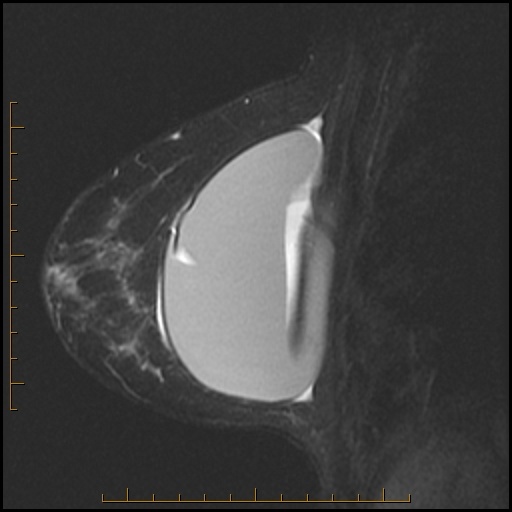

Name all the signs you can see on these sagittal T2 images from each breast. Next, name all the signs you can think of that signify MRI evidence of intracapsular implant rupture. Then be sure to scroll below the images to check your findings against mine.

Left breast (on right) is normal with physiologic radial folds (arrow).